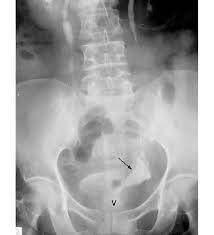

Clinically occult cervical cancer diagnosed after simple hysterectomy.

Be sure to talk with your health care team about the symptoms. Get detailed information about cervical cancer treatment in this summary for clinicians. Background occult invasive cervical cancer (oicc) is sometimes incidentally found in surgical specimens after a simple hysterectomy (sh). The preferred method of treatment in step ia1 is surgery; More than 40 years ago cervical cancer was a major cancer death risk for women.